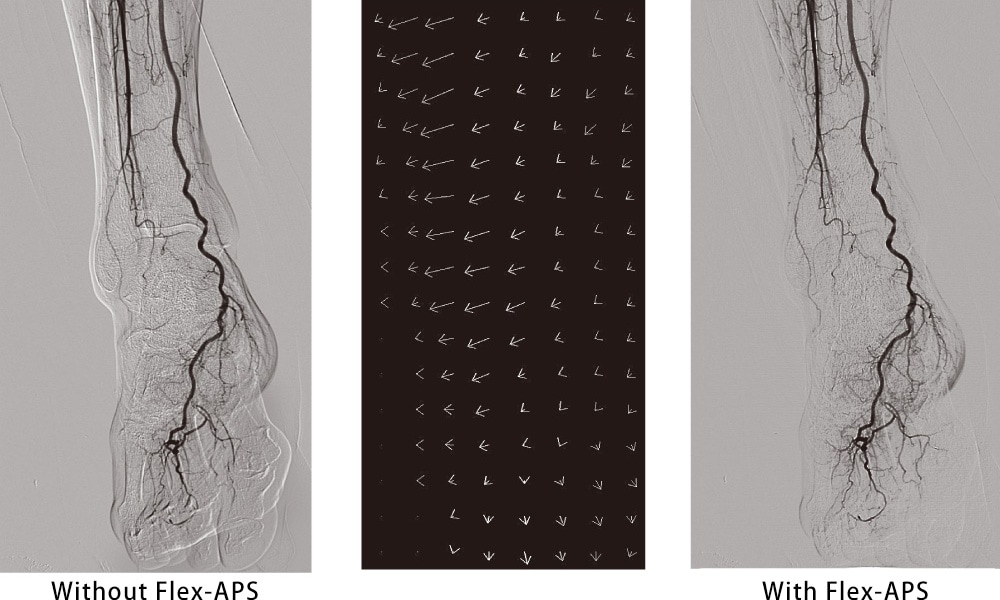

Real-time artifact optimization technique, "Flex-APS"

This technique is an automatic offset function for optimizing miss-registrations of DSA. Flex-APS automatically detects and optimizes the sectional pixel movement gap between MASK image and each frame image regardless of ROI's movement direction such as twisting.